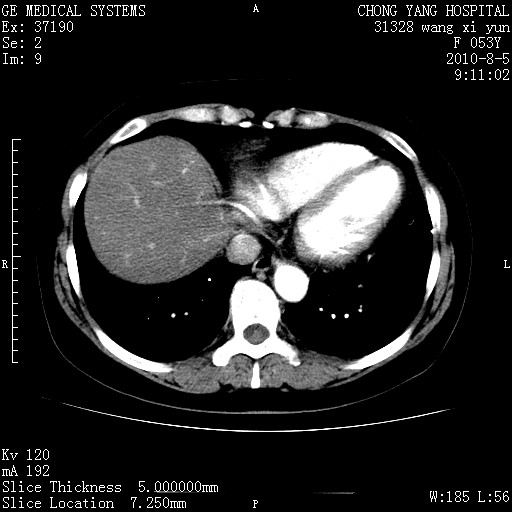

1)考虑肝左叶胆管细胞癌。2)脂肪肝。